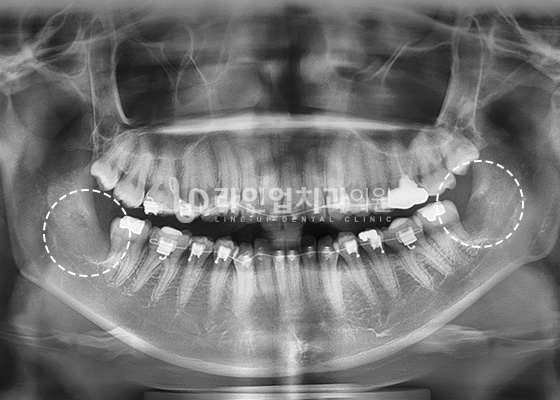

Case of Wisdom Tooth Extraction

Before

After